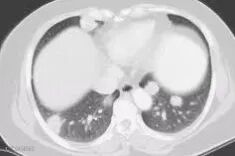

影像檢查:如CT掃描、MRI、骨盆超聲和胸部X光,以檢查是否有異常。